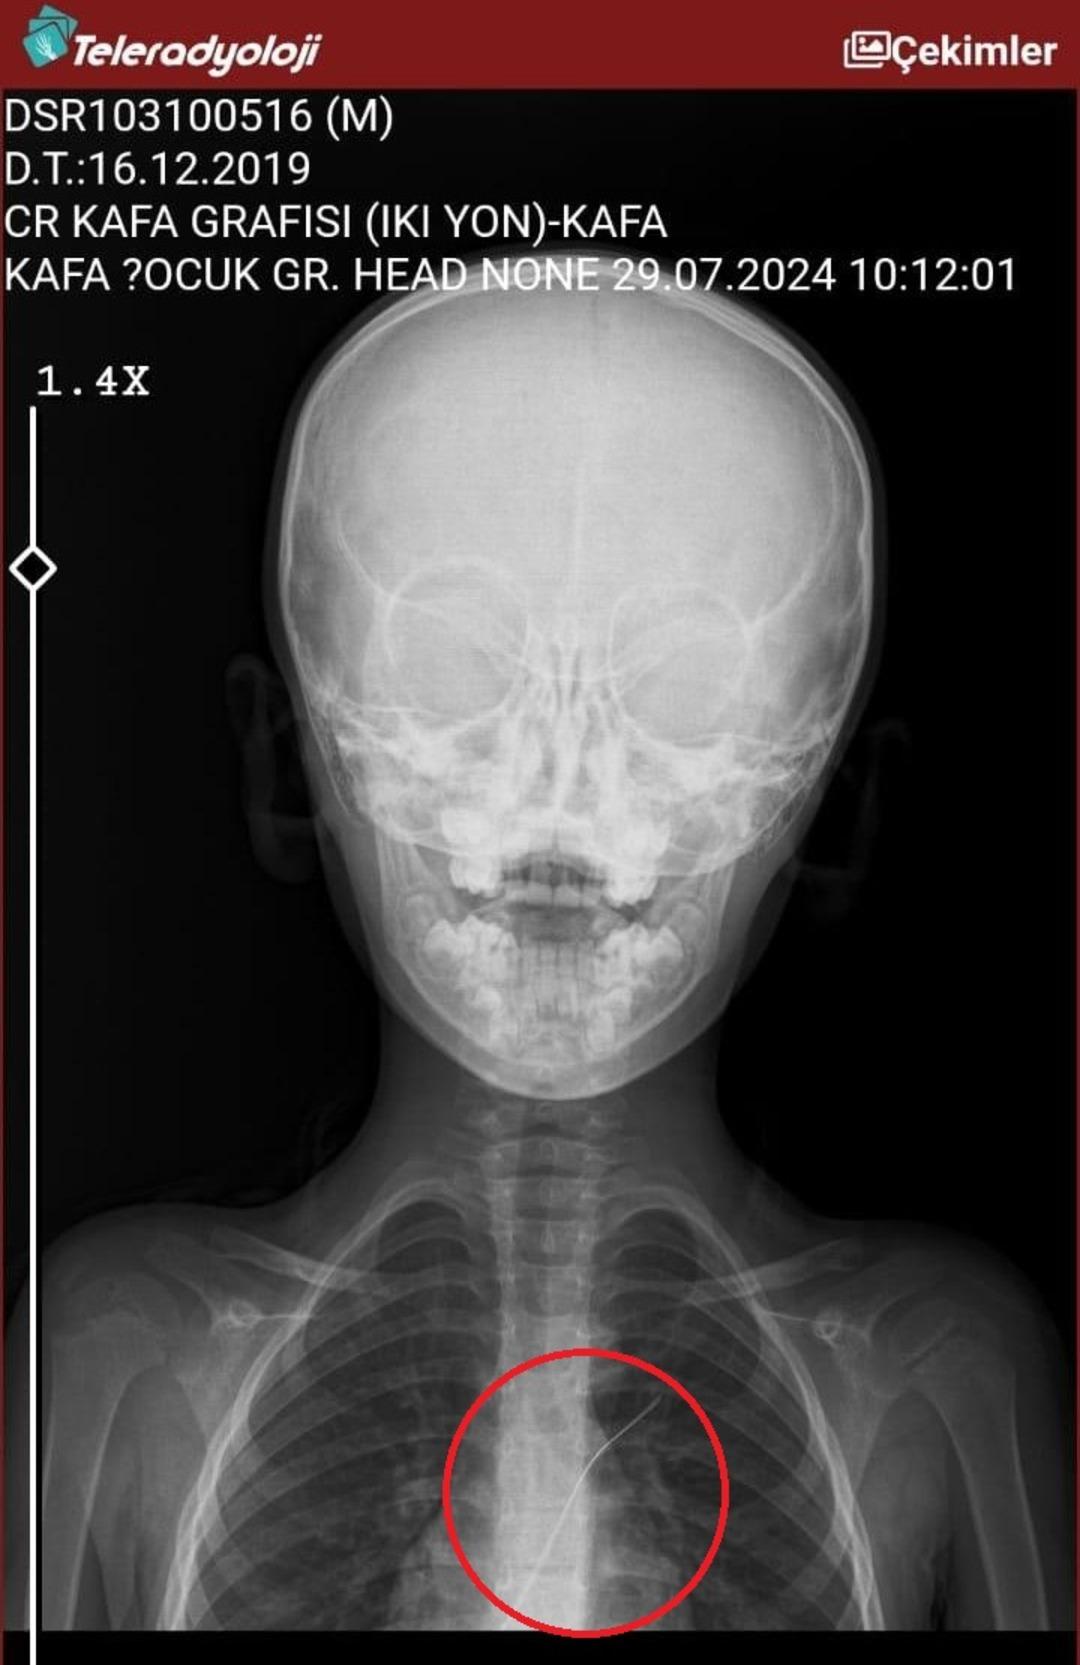

Seamore (37) ve Şaç’ta yaşayan Mehmet Ötün (40), Mayıs ayında bir parça salatalık yuttuktan sonra öksürük ve kusma şikayetleri gözlendiğinde Sernak Eyalet Hastanesine getirildi. Burada, ARAM gövdesinde yarıçap X ve manyetik rezonans görüntüleme unutuldu. Diyarbakir Gazi Yeşargil’in eğitim ve araştırma hastanesi jinekolojiye ve ARAM’lar için ek binaya yönlendirildi, 18 santimetrede 5.5 saatlik riskli cerrahi kaldırıldı. Postoperatif araştırmalarda, kateter kalp kapakına ve karaciğere zarar vermeye kararlıydı.

Aile avukatı Ahmet Yalçın, ikisinin de hastaneden şikayet ettiğini ve bir dava açtığını açıkladı ve şunları söyledi: “Müvekkilim Eylül 2022’de Stevens -Johnson’un kariyeri nedeniyle Eylül 2022’de Dicole’deki üniversite hastanesinde tedavi edildi. Kateter ona saldırıya uğradı.